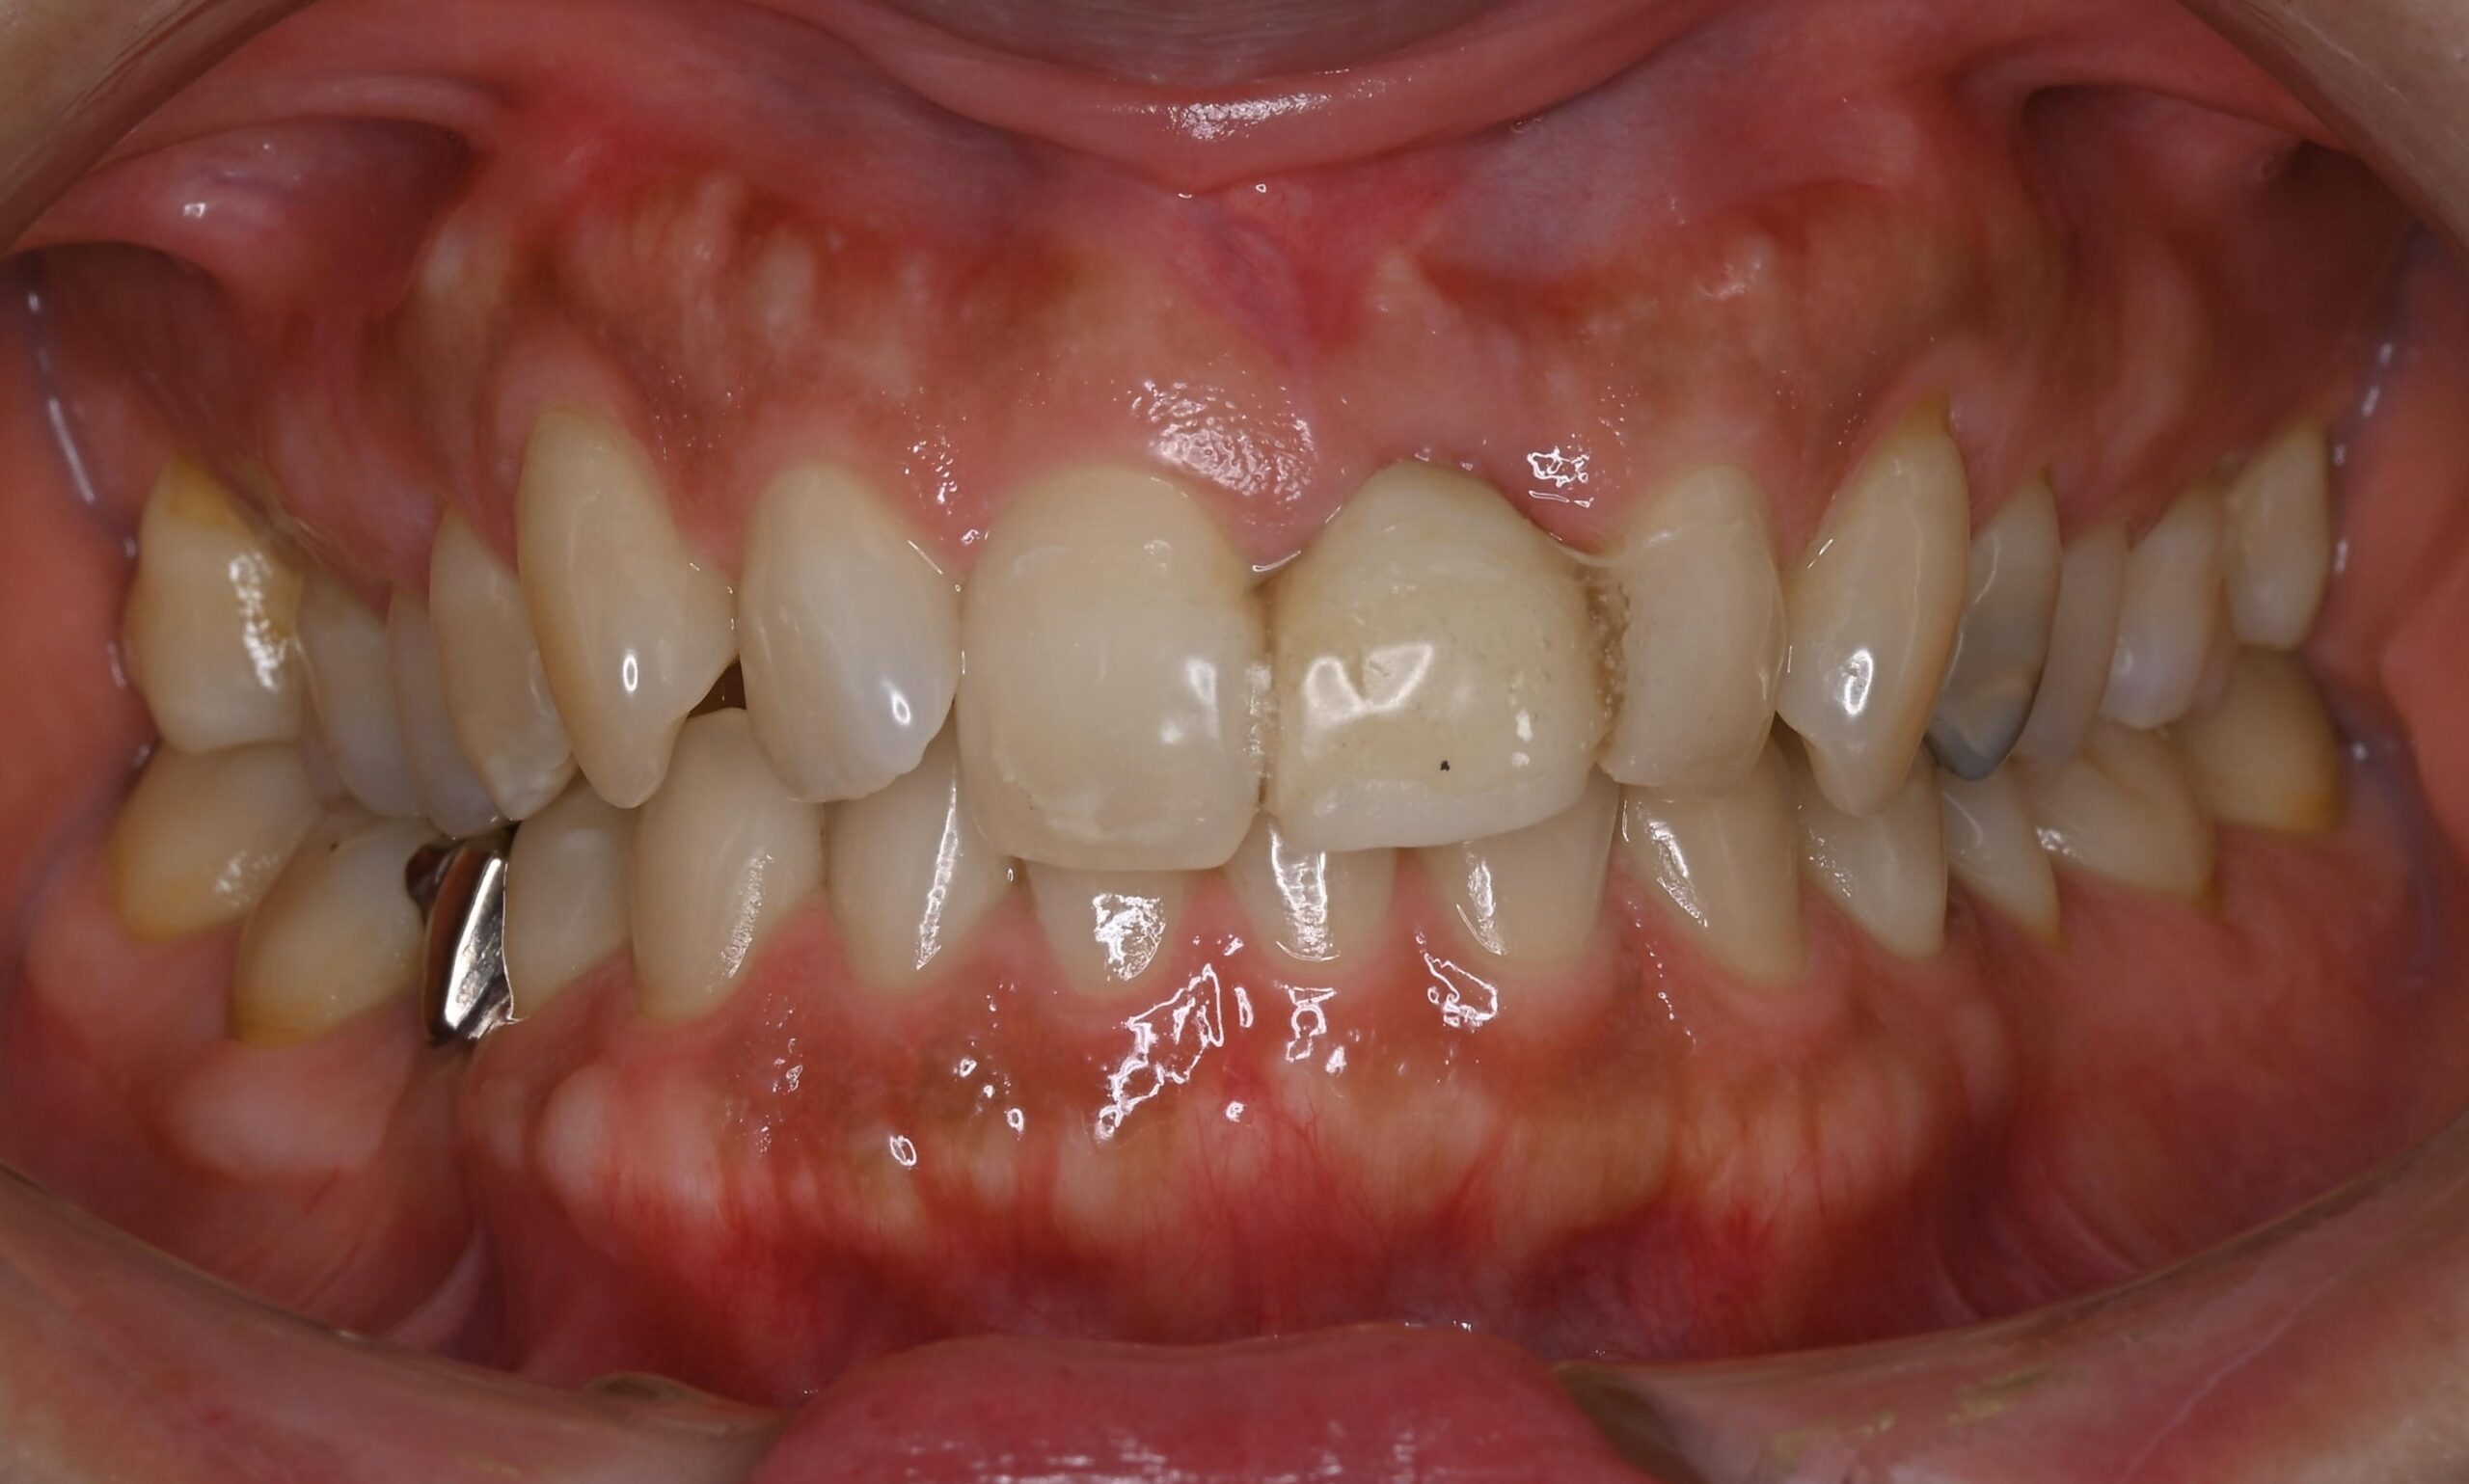

ジルコニアブリッジの症例

Before

After

• After

治療内容

左上1番を他院にて抜歯し、仮歯をボンドで固定された状態で来院されました。

歯を失ったところをブリッジで治す計画をたて、審美的な補綴を目指すためにホワイトニングから行いました。

最終的にジルコニアのブリッジを接着しました。

担当歯科医師:平沼 佳朗

治療期間・回数

約4回

費用

¥462,000

リスク・副作用

ごく稀にジルコニアの先端が割れることがあります。